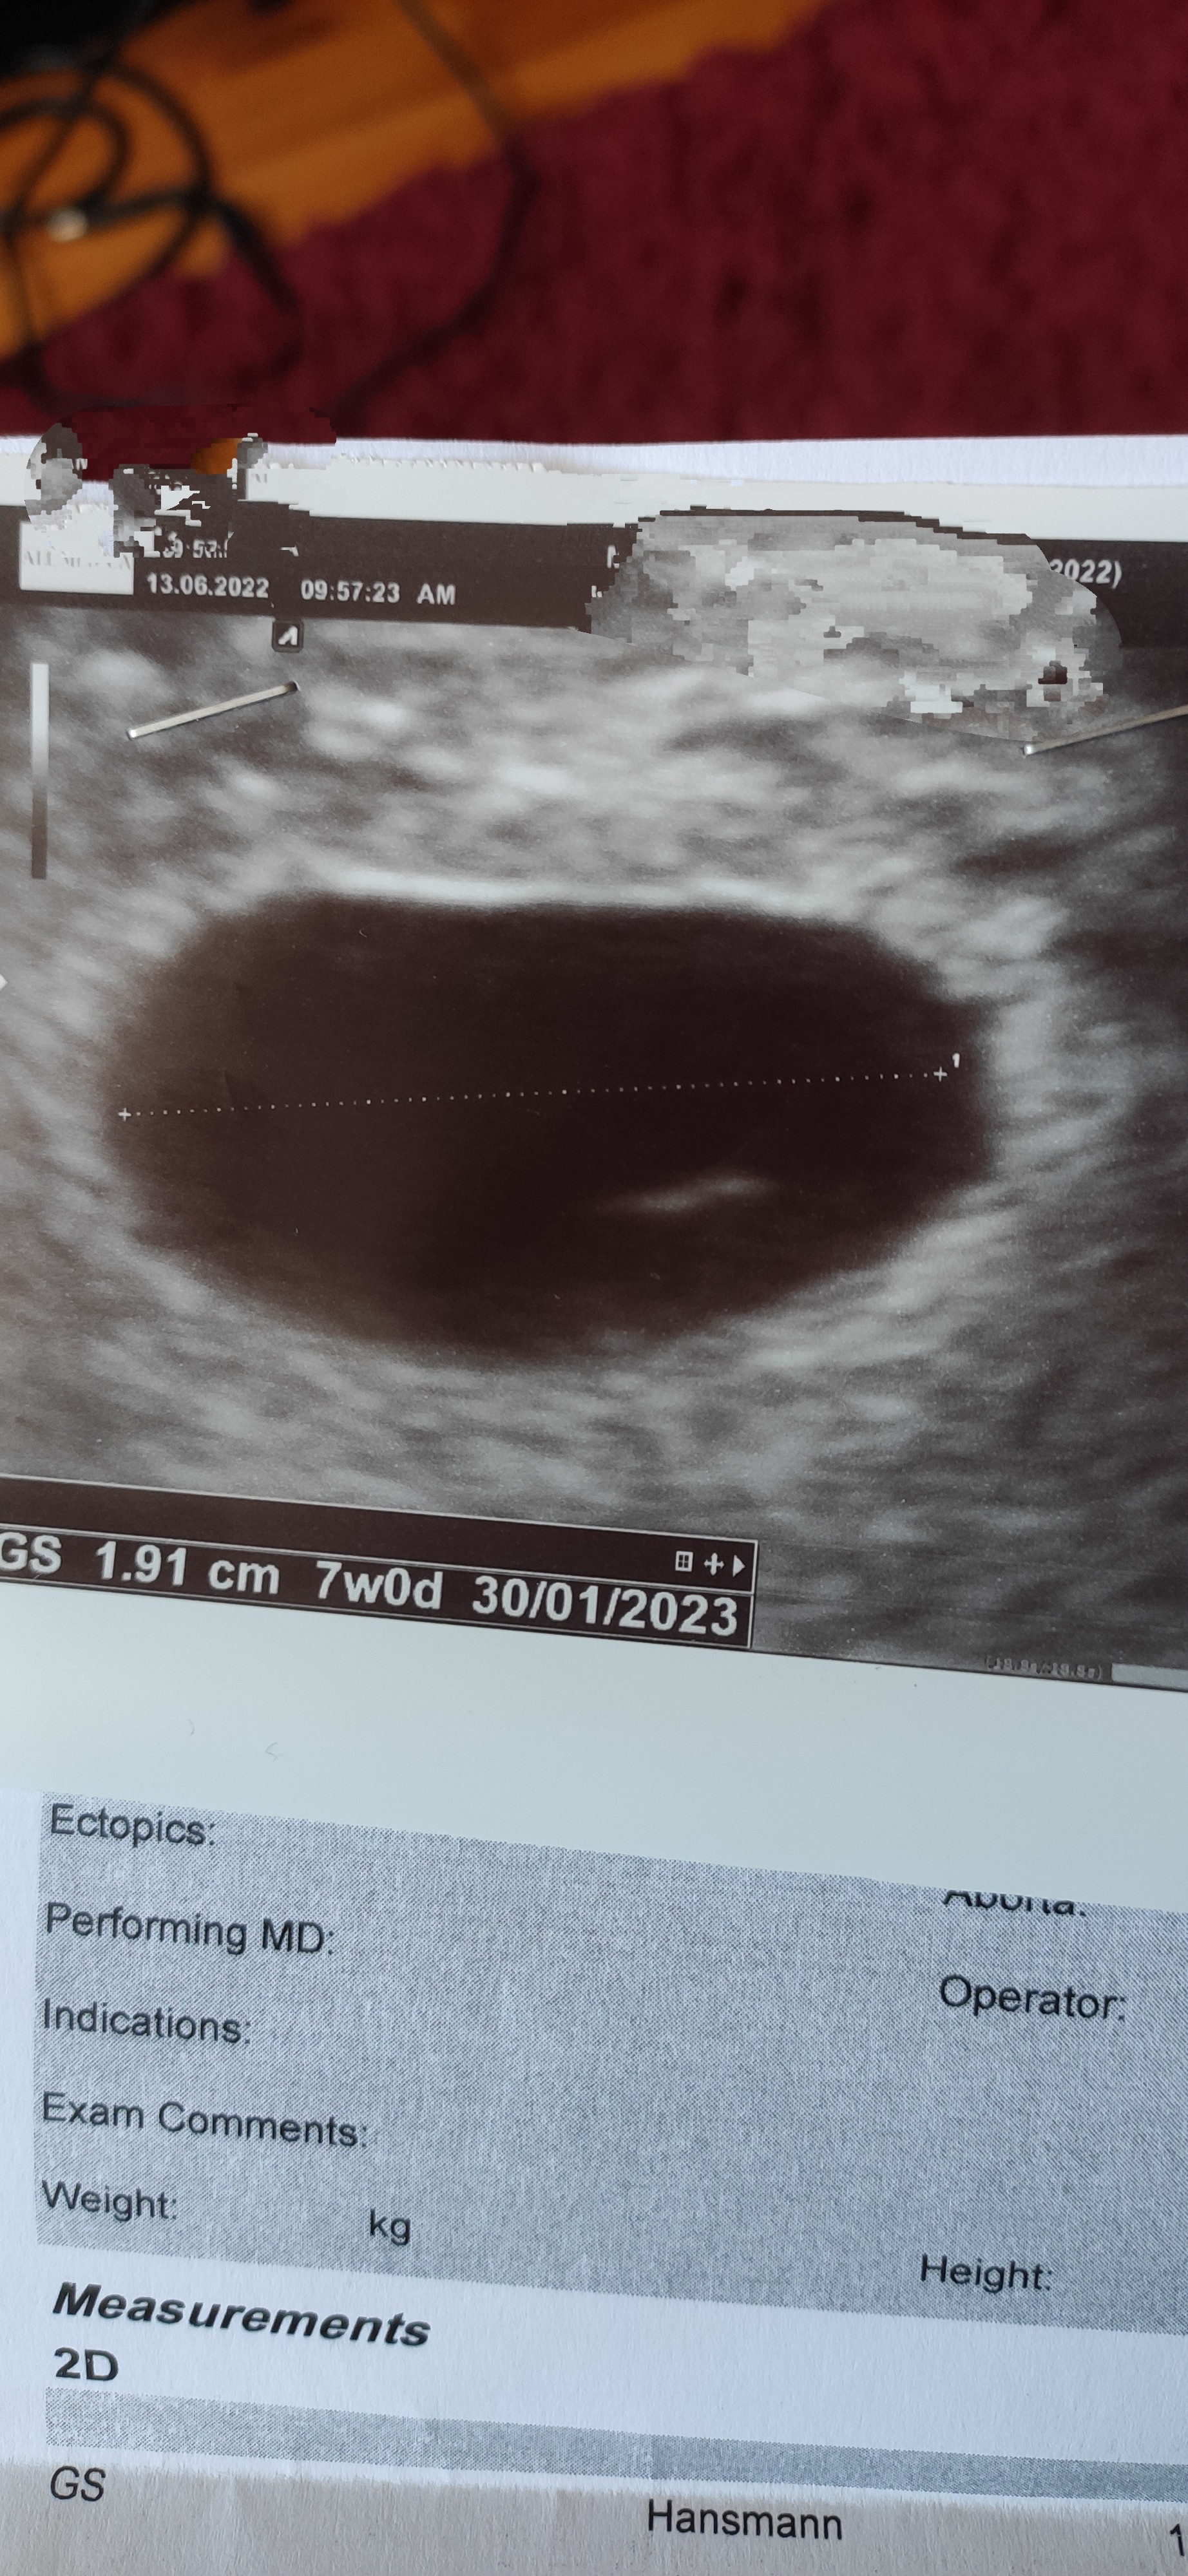

Hej. Ostatnią miesiączkę miałam 27.04, 28.05 wyszedł mi pozytywny test ciążowy, robiłam go w dzień planowanego okresu, 11.06 zrobiłam betę wyszła aż 33 000. Co nie zgadza mi się bo według bety to aż 7 tydz a jak dla mnie to jestem w ciąży max 5. Bo mam dłuższe cykle 32 dni. i owulacje mialam ok 13-15.05. 13.06 byłam na pierwszym USG, i tu zonk, puste jajo, tzn jakiś cień był ale nic poza tym. Idę na kolejne USG za 9 dni, przepisał mi luteinę. Martwię się i nie wiem co myśleć o tej wysokiej becie. Dodam, że mam objawy ciąży.